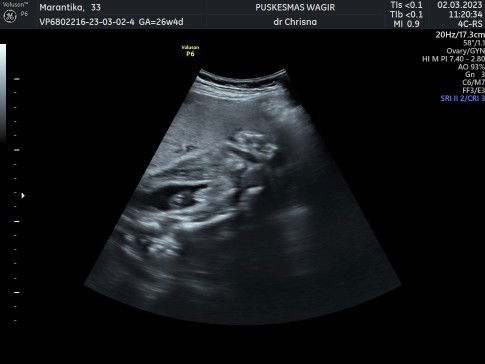

Hasil usg ada yg bisa baca atau sama mungkin ya?

Siapa ada tau ada yg sama.. Kata dokter cowok.. Berharap cowok, karena anak semua cewek.. Tapi cowok dan cewek sama aja yg penting sehat.. USG 28 minggu..